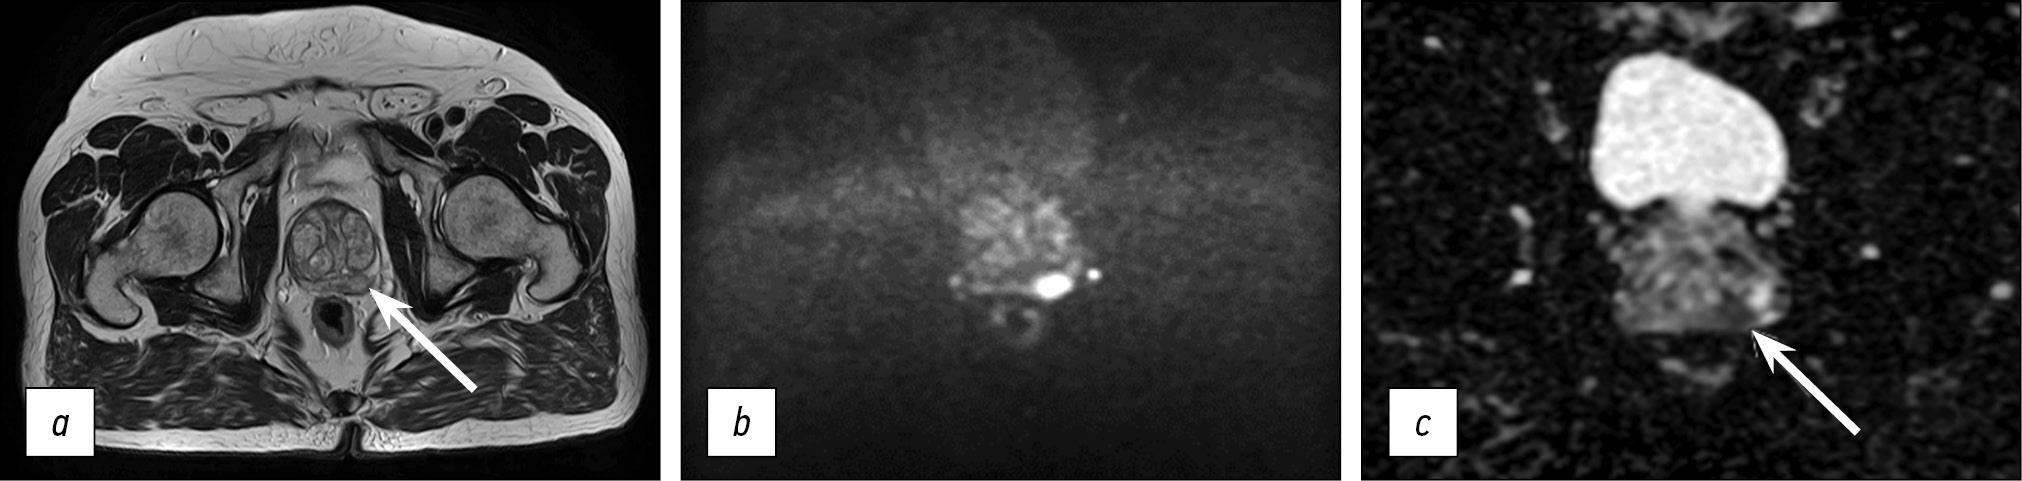

Fig. 3. Medical organization 2 (MO 2). In the peripheral zone on the right, a hypointense zone on T2-WI and ICD map adjacent to the capsule (arrows) is defined: a) T2-WI, axial projection (TR 6006, TE 75, FOV 30×25 cm, Matrix 256×256); b, c) DWI and ICD (TR 9377, TE 80, FOV 37×30 cm, Matrix 128×192).

Note. Here and in Figures 3–5: T2-WI, T2 weighted images; DWI, diffusion-weighted images; MDC, measured diffusion coefficient; TR, repetition time; TE, echo time; FOV, field of view; Matrix is a matrix.

Thus, in all presented HO MHD, the requirements recommended by PI-RADS v2.1 for the presence of T2-WI in the axial and at least one additional (sagittal and/or coronal) views were met. In addition, it should be noted that the recommended layer thickness for T2-WI in the axial view should be no more than 3 mm, while in HO 2 and HO 3, it is 4 mm (Figures 3 and 4). The same is true for HO 1, where the DWI slice thickness is 5 mm with the recommended 4 mm or less (Figure 2). An important factor is the field of view; according to PI-RADS v2.1, field of view (FOV) values for T2-WI should be 12–20 cm, while in HO 1 and HO 3, the field of view is much larger (30 × 35 cm and 40 × 30 cm, respectively) (Figures 2 and 4). According to PI-RADS v2.1, the recommended field of view for DWI is 16–22 cm, although none of the three HOs adhere to this standard. The fact of the variability of the FOV values and the section slice thickness inevitably affects the resolution and, as a result, the ability to detect lesions.